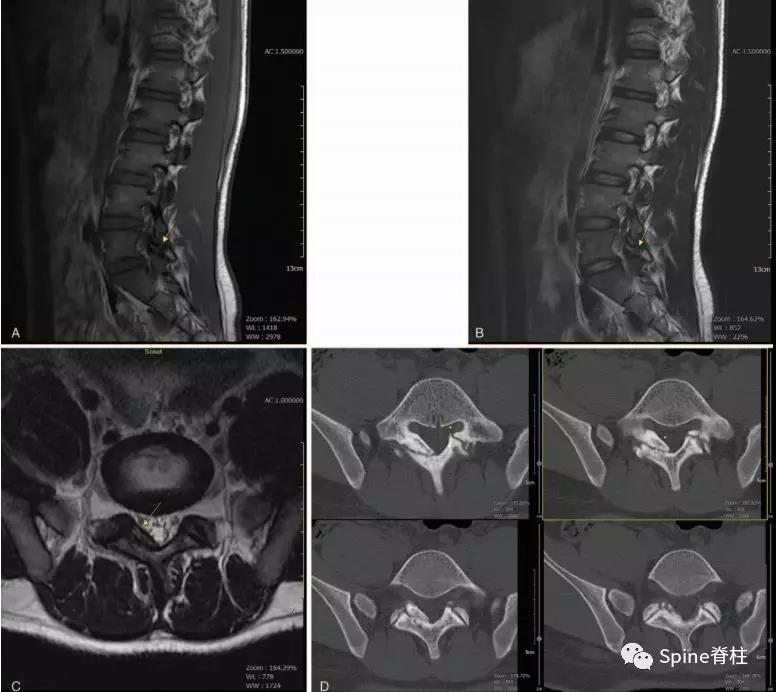

图:17岁腰痛男孩,L5双侧峡部裂和右侧椎板裂C:右侧椎板增厚,不连续

图:L5半椎板裂

17岁芭蕾舞者,腰痛7个月

CT示:左侧为椎板裂(箭头),右侧为峡部裂(箭头)

图:L5半椎板裂15岁篮球运动员,严重腰痛,影响睡眠CT示:左侧为椎板裂(箭头),右侧为峡部裂(箭头)

图:L5全椎板裂15岁相扑运动员,严重腰痛,后伸明显加重正侧位X线示椎板水平骨折线(白箭头)。MRI示T2椎板高信号,T1椎板低信号

图:L4全椎板裂16岁男孩,3年严重腰痛,后伸受限其中L5椎体骶化